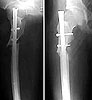

femur

humerus

tibia

The patient came to me two days after injury. Her general condition was not good with Hb 6.7 gm%. After Blood transfusions in the first stage I did standard femoral Interlocking - 10mm nail with two proximal screws. 3 days later I did Tibial and Humeral Interlocking nailing - 8mm and 6mm nail respectively with proximal locking only.

On discharge 10 days later she wass walking independently with Zimmer frame with full knee hip and shoulder movements. Xrays are attached.